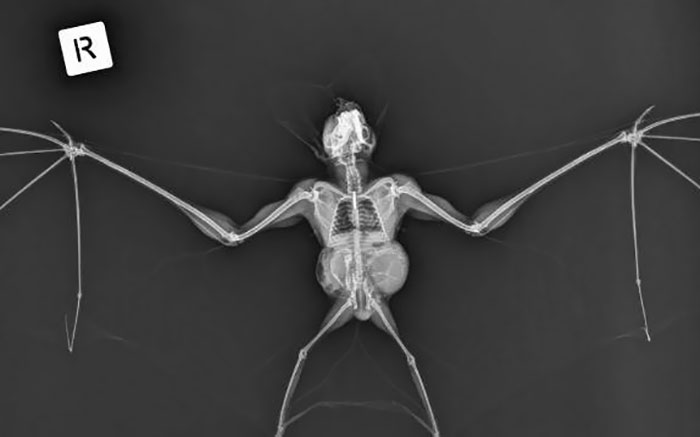

An X-Ray Of A Ghost Bat